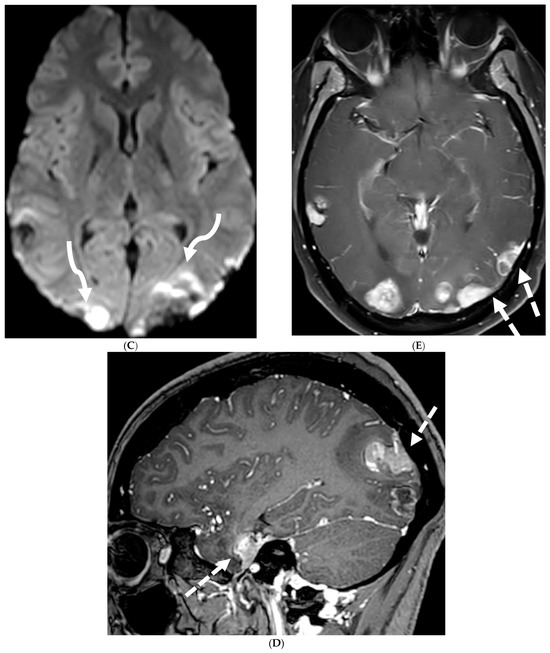

4.4. Systemic Meningeal Metastases (SMM)

Meningeal metastases from an extracranial primary tumor is a diagnosis with a grave prognosis, reducing the survival to less than 3 months if left untreated. Early and accurate diagnosis is essential for improving patient outcomes [84]. Leukemias and neuroblastoma are the most common primary malignancies in the pediatric population [85,86]. Leukemia is the only one which merits prophylactic treatment to avoid SMM.

The typical MRI presentation of SMM involves serpentine, nodular, or plaque-like enhancement in sulcal spaces, basal cisterns and along the cauda equina nerve roots [87,88]. Notably, SMM enhancement on post contrast [PC]-T1 images is superior to the PC-FLAIR in contrast to that seen in infectious meningitis [84]. However, in case of a non-enhancing primary tumor, FLAIR and DWI are important sequences to look for SMM. Hydrocephalus and subependymal deposits are other common features found in kids with SMM (Figure 15, Figure 16 and Figure 17). Positive cytology on CSF analysis, especially with leukemia, is important [89].

Figure 15.

Axial DWI (A), axial ADC (B), axial T1 FS post contrast (C) and Fluorodeoxyglucose Positron Emission Tomography (FDG–PET) scan (D): 13-year-old male with bilateral leg pains, headache, fever and weight loss: Blood tests and CT scan were concerning for Burkitt’s lymphoma. There is heterogeneous calvarial bone marrow signal with restricted diffusion (arrows) and patchy enhancement (curved arrows). Diffuse thickening and enhancement of pachymeninges in the supratentorial compartment is noted (dashed arrows). Findings are most consistent with lymphomatous involvement. Multifocal diffuse/heterogeneous pattern of FDG uptake within the axial and appendicular skeleton and the calvarium (open arrows). Intense FDG avid uptake is seen in the presacral mass (star).

Figure 16.

16-year-old female with 4 months history of globus sensation and recent botox injection of lower esophageal junction. Headache and vomiting for past week: Esophagogram (A), Axial T2 orbits (B), axial FLAIR (C) and post contrast T1 (D,E): Narrowing of the Gastroesophageal (GE) junction with beaked configuration and mild distention of the lower esophagus likely from early achalasia (black arrow). There is bilateral papilledema indicating raised ICP (dashed arrows) and sulcal hyperintensity (curved black arrows). Diffuse LME in the supra-and-infratentorial regions and along optic sheaths raising the concern for leptomeningeal carcinomatosis (white arrows). Pathology: Gastric adenocarcinoma metastasis.

Figure 17.

Axial T2 FS (A), axial Susceptibility weighted imaging (SWI) (B), axial DWI (C), post contrast sagittal and axial T1 post contrast (D,E): 19-year-old female with history of stage IV neuroblastoma, left paraspinal primary ganglioneuroblastoma, treated with chemotherapy, radiation and bone marrow transplant presents with headache. There are extensive hemorrhagic leptomeningeal masses, both supra and infratentorial region (arrows). The lesions also demonstrate restricted diffusion which could be secondary to internal hemorrhage or high cellularity of the tumor(curved arrows). The larger masses invade the cortex of both cerebral hemispheres, with surrounding vasogenic edema (black arrow). Avid enhancement of the lesions is seen along with overlying dura (dashed arrows). Features are in keeping with extensive leptomeningeal metastatic neuroblastoma.